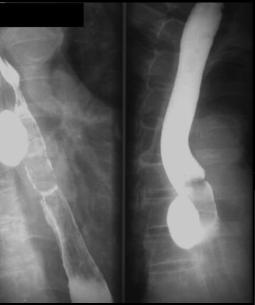

Image TOGD d'une megaoesophage sur

le cliche de face et OAD . Bord lisse et

aperistaltisme ., la retressisement a inferieure est

image en queue de radis |

Megaoesophage en face

et en profile OAD |

A etat tardive oesophage dilate et

alonge en forme de petit chaussette . |